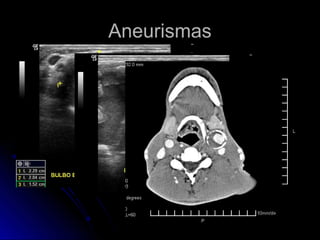

AneurismasAneurismas